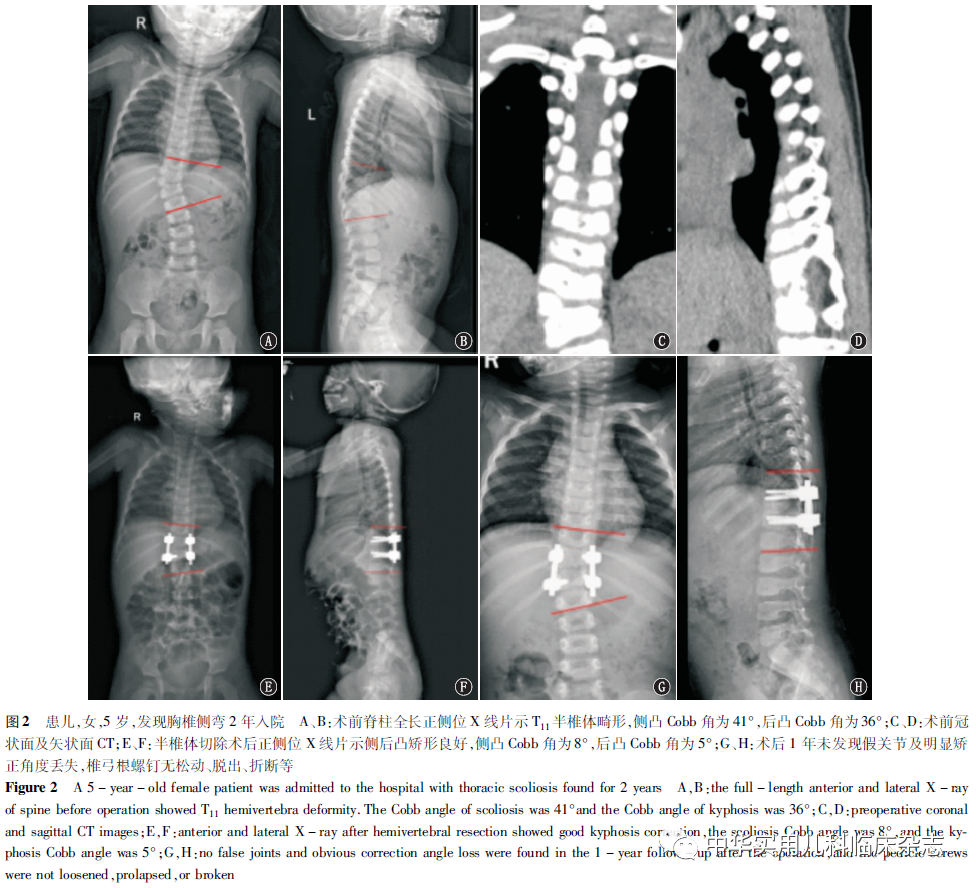

结果本组患儿手术时间(216.9±28.3) min(172.0~262.0 min);术中出血量(478.5±132.6) mL(370.0~850.0 mL);固定融合节段为(3.3±0.8)个(2~6个)。13例患儿共置入85枚椎弓根螺钉(0级78枚,1级3枚,2级4枚),准确置钉81枚,置钉准确率为95.3%,无因位置不佳而需重置者。术后脊柱侧凸Cobb角矫正率为(78.4±5.9)%,后凸Cobb角矫正率为(72.6±7.0)%。术后及末次随访时侧、后凸角度及VAS评分、ODI指数及 SRS-22 评分与术前比较,差异均有统计学意义(均P<0.05);术后与末次随访时比较,差异均无统计学意义(均P>0.05),见表1。术后出现切口感染1例,应用抗生素2周好转;2例术后出现单侧下肢麻木,1周缓解。患儿均未出现严重神经或血管损伤等并发症。术后随访6~18个月,平均12.3个月,术后及随访期间未发现假关节及明显矫正角度丢失,未出现内固定失败案例,典型病例见图2。

讨论3.1 半椎体切除术的手术方式及手术时机 半椎体所致先天性脊柱侧后凸的治疗原则为防止进展、改善畸形,保守效果不佳,多采用手术治疗。目前常用的术式有原位融合术、半侧骨骺固定术和半椎体切除术。后路半椎体切除因其具有矫形效果好、创伤小等优势,逐渐成为治疗半椎体畸形的主流术式[12]。半椎体切除术包括前后路和单纯后路切除术2种。随着内固定器械和半椎体切除技术的发展,多数脊柱外科医师更倾向于后路手术。对于T4以上半椎体患者,半椎体后路切除效果更佳,因其避免了在联合入路时损伤过多的肌肉[13]。既往研究表明,侧凸的术后改善情况与患儿的发病年龄和侧凸程度相关[14]。关于其切除时机,有学者认为4岁前切除可获得较好的矫形效果,并降低神经系统并发症的发生率[1]。多数情况下,为防止畸形进一步进展,纠正躯干失衡,建议早期手术来提供稳定性。Chang等[2]研究发现,在6岁前接受手术治疗的患儿其矫形效果显著,对椎体或椎管的生长未发现负面影响。但也有文献报道椎弓根螺钉可能无法为年龄太小的儿童提供足够的稳定性,可引起与植入物相关的并发症[15-16]。李海侠等[17]认为5~8岁行半椎体切除的安全性及配合度更高,对于婴幼儿先天性脊柱畸形,可保守治疗至5~8岁再择期行手术治疗。本组患儿年龄5~14岁,平均9.9岁,术后矫形效果显著。3.2 儿童半椎体切除术 置钉的困境为半椎体周围毗邻结构复杂,且儿童椎弓根细小,周围软骨较多,置钉失败或置钉引起周围神经血管损伤常导致严重后果。由于患儿年龄小,椎弓根皮质柔软且部分伴发育异常,在置钉过程中易导致椎弓根骨折,再加上有些患儿发育畸形,术中定位困难,置钉时螺钉误入椎管可能会导致脊髓或神经损伤。Guo等[15]报道116例后路半椎切除术的并发症发生率为9.5%,其中63.6%与内植物有关。Shono等[18]报道12例行后路半椎体切除术,侧凸的矫正率为64.0%,后凸矫正率为57.5%。Yu等[19]报道半椎体切除术后的矫正率为68.5%。Yang等[20]报道10岁以下儿童后路半椎体切除术后主弯矫正率术后为68.5%,末次随访时为52.9%;考虑曲度进展的原因可能与半椎体切除不全、畸形复位不充分有关。本组患儿均采用后路一期半椎体切除,未出现血管及严重神经损伤等并发症。术后侧凸矫正率为(78.4±5.9)%,后凸矫正率为 (72.6±7.0)%,末次随访时保持稳定,随访中未出现内固定失败者,矫形效果较好,总体疗效满意。3.3 3D打印预置钉道模型在半椎体切除术中的应用价值 可靠的椎弓根螺钉固定是手术成功的关键和基础,传统的徒手置钉难度大、风险高,如何提高置钉的准确率一直是脊柱外科医师所面对的难题。近年来,学者探索采用不同的方式来辅助椎弓根置钉,置钉成功率得到明显提升。Xu等[21]报道69例徒手与导航椎弓根螺钉置入的准确率分别为63.8%和97.8%。Shree Kumar等[22]在219例病例中通过导航辅助置入1 152枚椎弓根螺钉中,颈椎、胸椎和腰椎置钉准确率分别为93.0%、96.3%和96.4%。有学者研究发现,机器人辅助置钉准确率为90.0%,徒手置钉准确率为73.5%[9]。在半椎体切除中应用 3D打印技术辅助置入椎弓根螺钉的成功率为95.56%[22]。Lu等[23]使用带双侧导向孔的3D打印模板置入84枚椎弓根螺钉,有82枚完全在椎弓根内,2枚螺钉穿透椎弓根壁≤2 mm。本组病例在3D打印预置钉道模型辅助下共置入椎弓根螺钉85枚,置钉准确率为 95.3%。这与以往报道[22-23]结果类似。3D打印预置钉道模型相对于其他智能化工具,价格适中,操作简单,可减少术中透视次数。但3D打印技术也有一定的不足:(1)准备时间长:从拍摄CT获取原始数据到制作出模型需要一定的时间,术前还需进行低温等离子消毒,在急诊手术中很难应用;(2)需要具备一定的基础:需要医师熟练掌握相关软件的操作,且具备一定的脊柱外科专业知识;(3)存在一定的误差:模型的设计及打印机在制作过程中因精度不同会产生一定的误差。本研究相对存在一些局限性:纳入病例的数量较少;本研究为单中心研究;随访的时间不足;后续仍需要长期的随访观察。综上,对于单发性完全分节型先天性半椎体患儿,术中应用3D打印预置钉道模型辅助后路半椎体切除及椎弓根置钉临床疗效确定,有较好的安全性、可靠性,提高了螺钉置入的精准性,可有效改善患儿和畸形,同时该技术操作简单、经济实用,值得在临床应用。